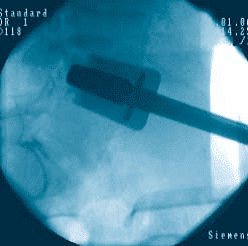

Watch the prodisc L Surgical Technique:

prodisc L Gallery

Click to enlarge image